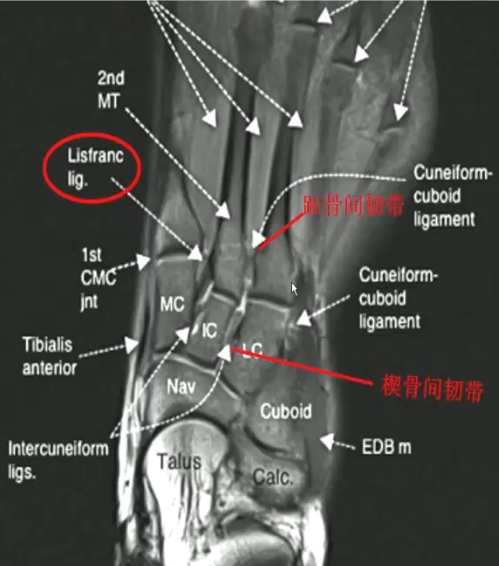

Lisfranc韧带:

> 起自内侧楔骨,附着于第2跖骨底内侧

> 阻止第2跖骨外移